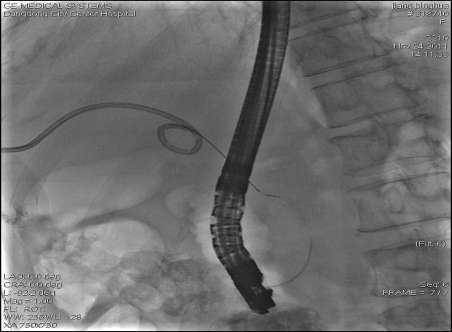

我院消化内科ERCP双对接技术已达到省级标准

2012-10-26